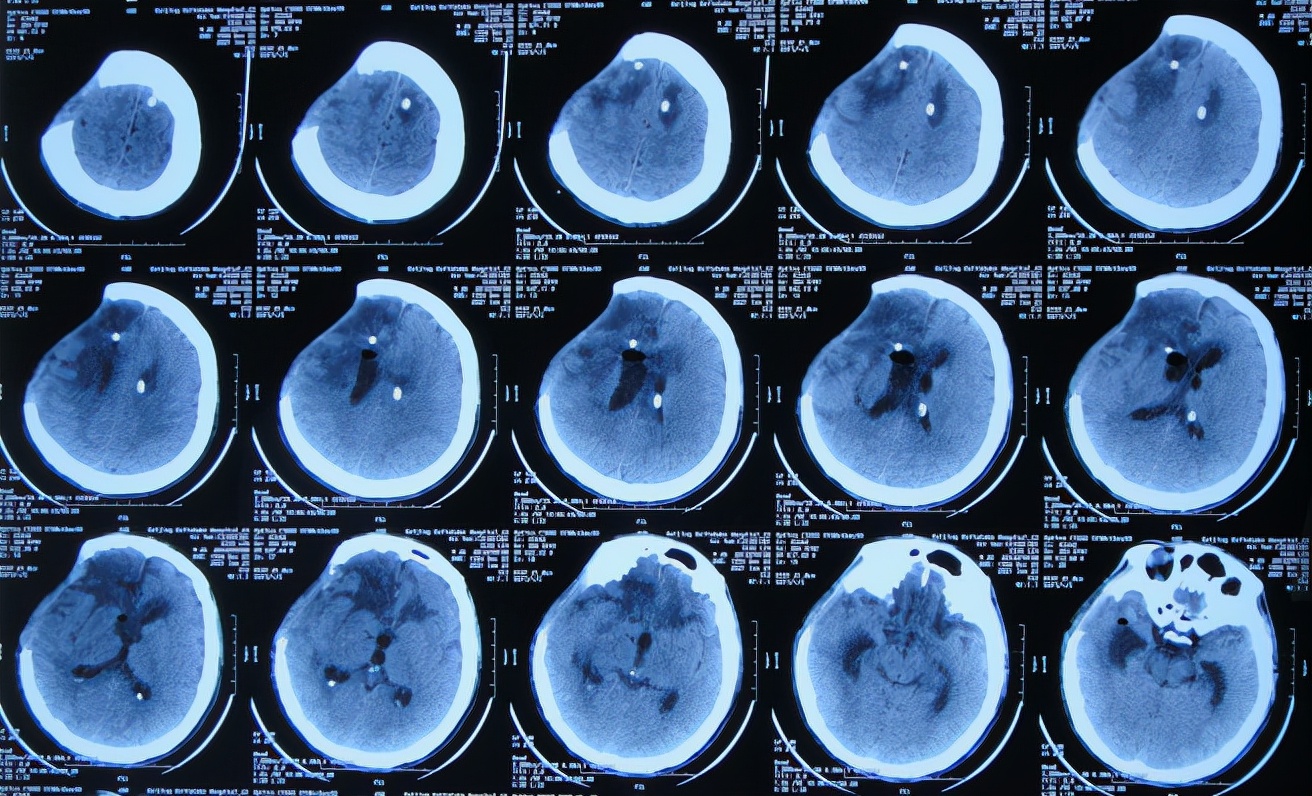

患者于2020年12月12日,在工作时意外从货车上摔下致头颅受伤,出现意识不清,送至河北省定兴县某医院,急诊查头颅CT示颅内血肿,中线有偏移( 图-1 ),给予开颅颅内血肿清除术+去骨瓣减压术,留置引流管,并行气管切开术;术后当天查头颅CT示开颅术后状态( 图-2 ),转入ICU病房。

图-2: 2020年12月12日开颅术后头颅CT

开颅术后次日,出现发热的症状,开颅术后3天即2020年12月15日,拔除了头颅引流管,头颅CT示仍水肿,稍有脑膨出( 图-3 )。

图-3: 2020年12月15日头颅CT